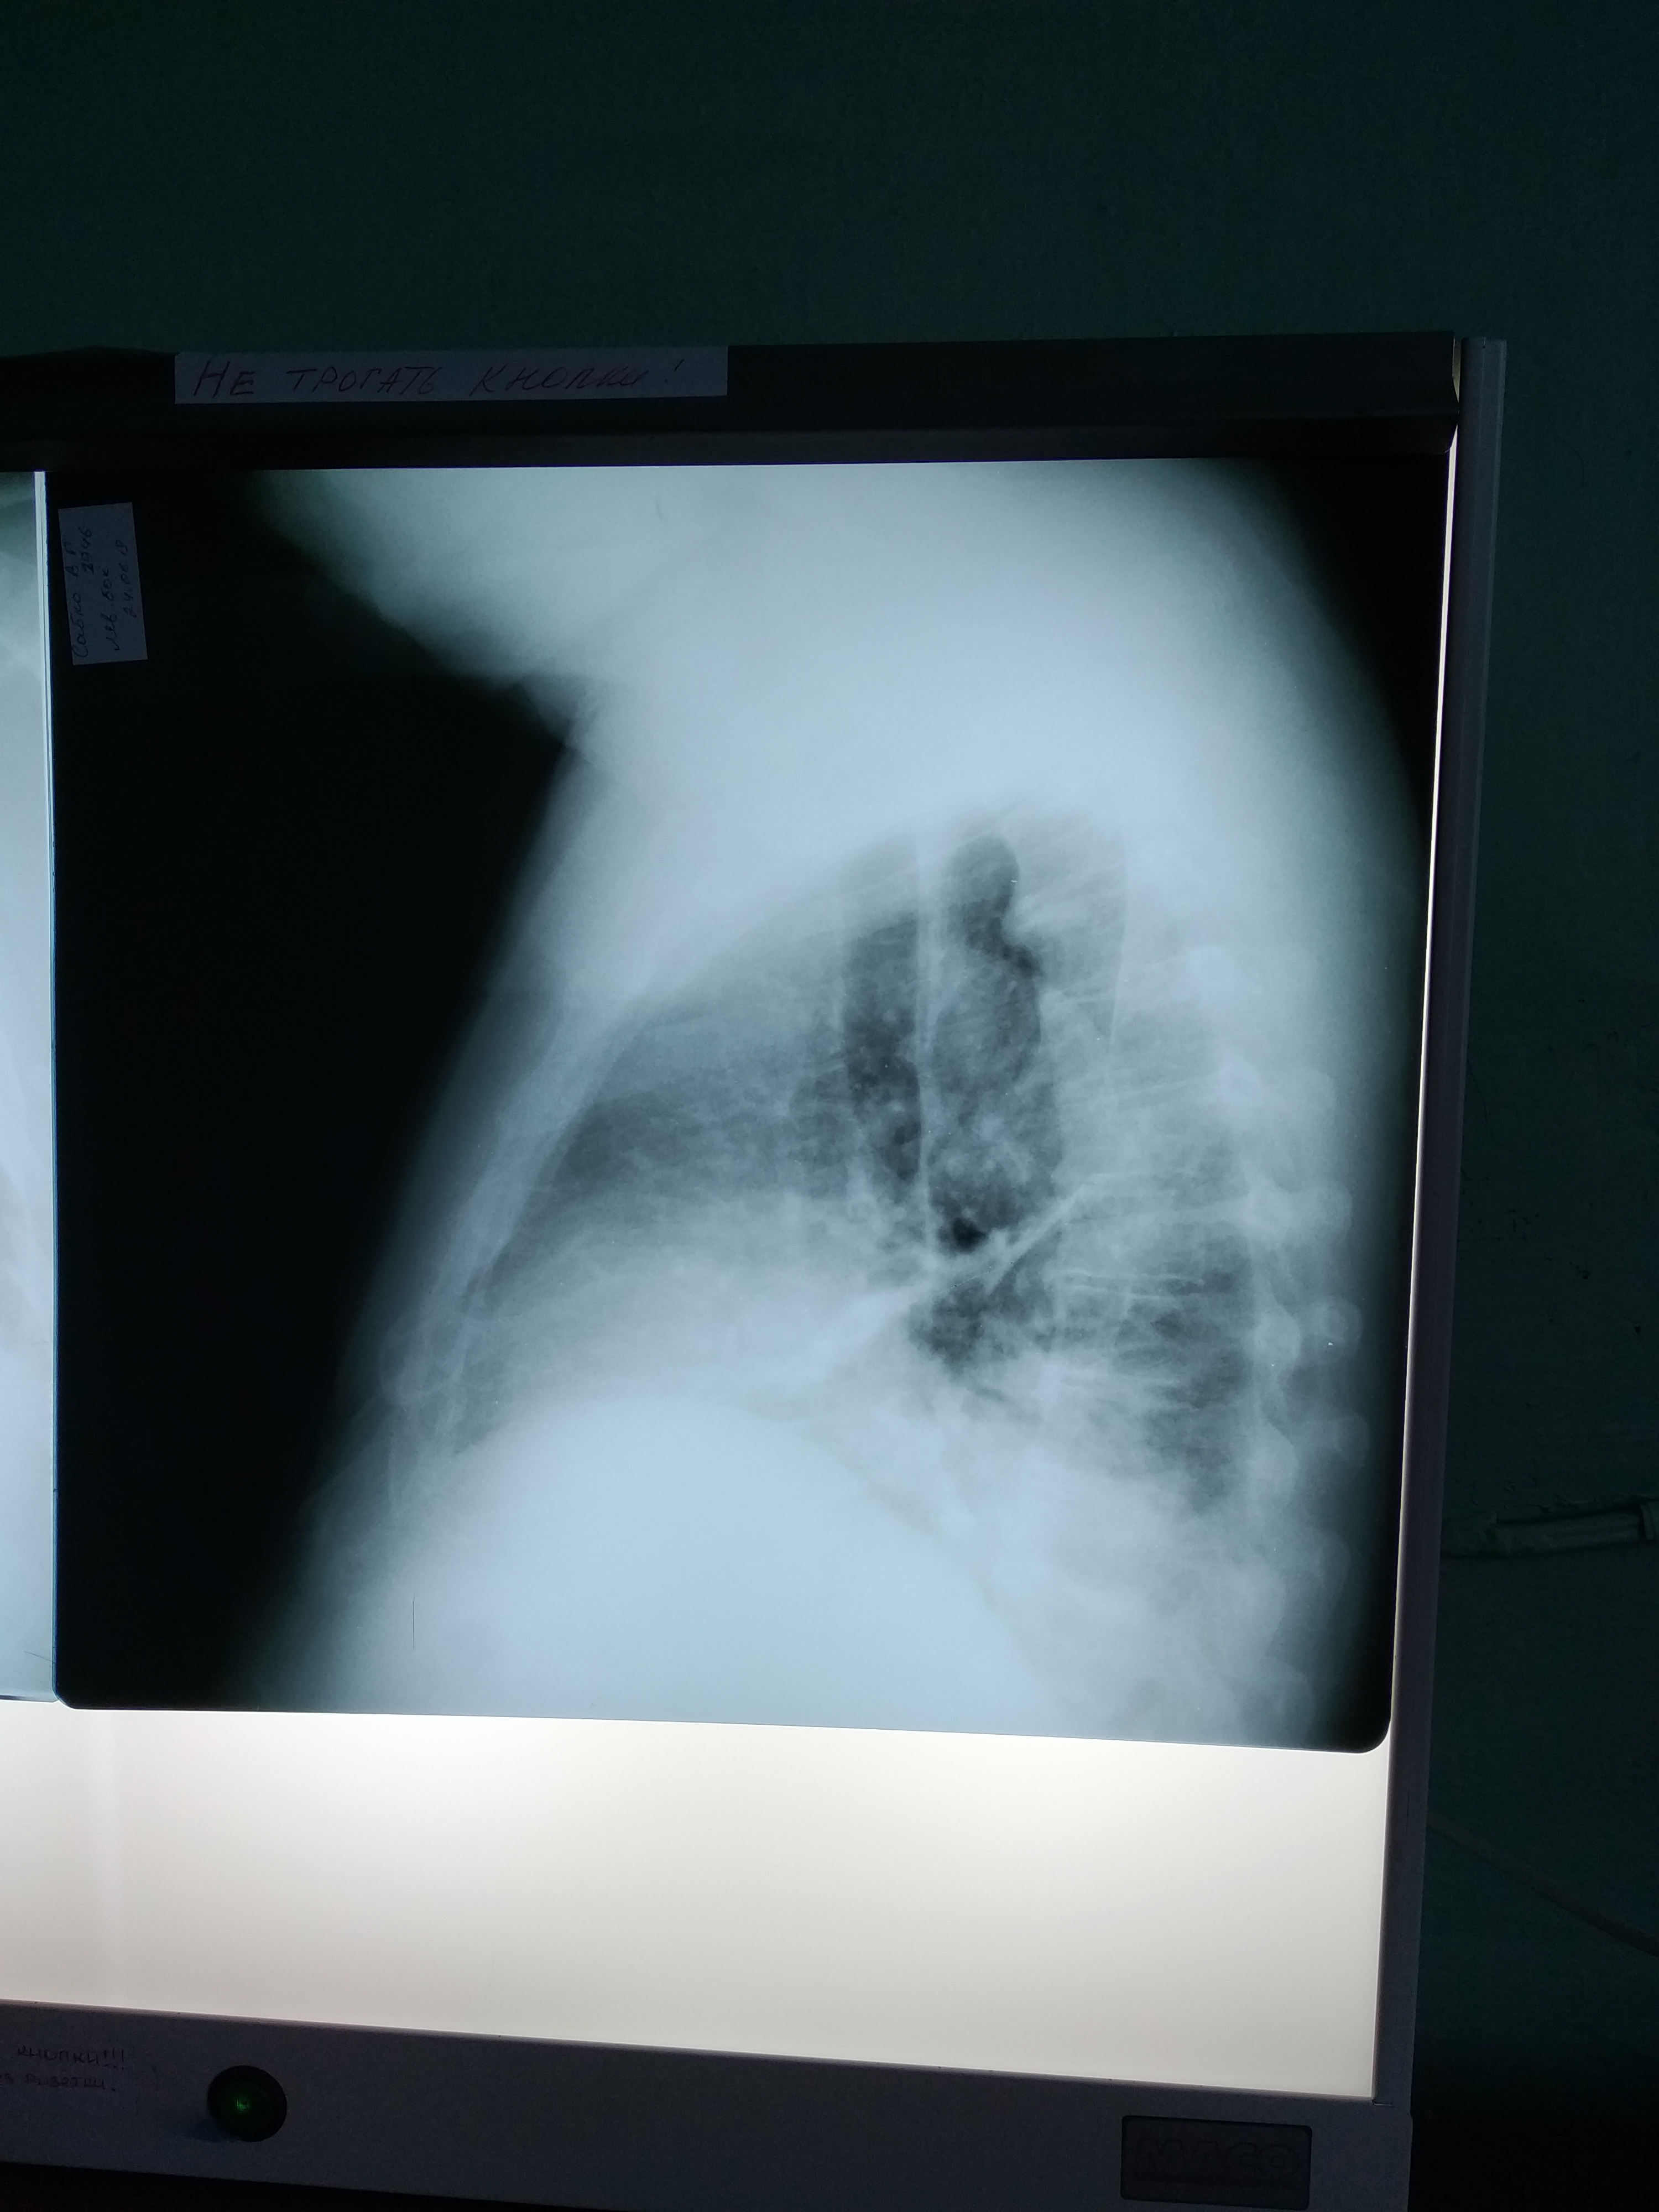

Похоже на опухоль с распадом и нагноением, ателектаз, гидроторакс/плеврит.

Рентгенограмму покажете?